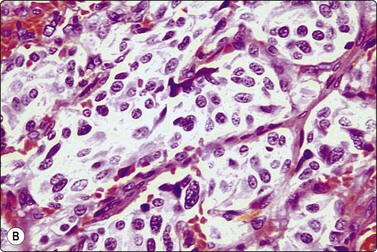

Acinic cell carcinoma (Figs 4.48-4.50)129,130

image image

Fig. 4.48 Acinic cell carcinoma

Epithelial fragments composed of cells with abundant vacuolated cytoplasm and relatively bland nuclei, resembling normal acinar cells; many naked nuclei; scanty, thin fibrovascular stroma. Note absence of well-formed acinar structures (A, MGG, IP; B, Pap, HP).

image

Fig. 4.49 Acinic cell carcinoma

Cells with oncocyte-like cytoplasm, distinction from oncocytoma difficult (MGG, HP).

Fig. 4.50 Acinic cell carcinoma

A less well-differentiated tumor may be difficult to type as acinic cell carcinoma. Ancillary techniques such as EM may help (MGG. HP).

Criteria for diagnosis

Abundant cell material with a clean background,

Cells mainly in clusters, scanty inconspicuous fibrovascular stroma,

Microacinar groupings,

Abundant, fragile, finely vacuolated, occasionally dense oncocyte-like cytoplasm,

Rounded, medium-sized nuclei, mild to moderate anisokaryosis, bland chromatin,

Many stripped nuclei.